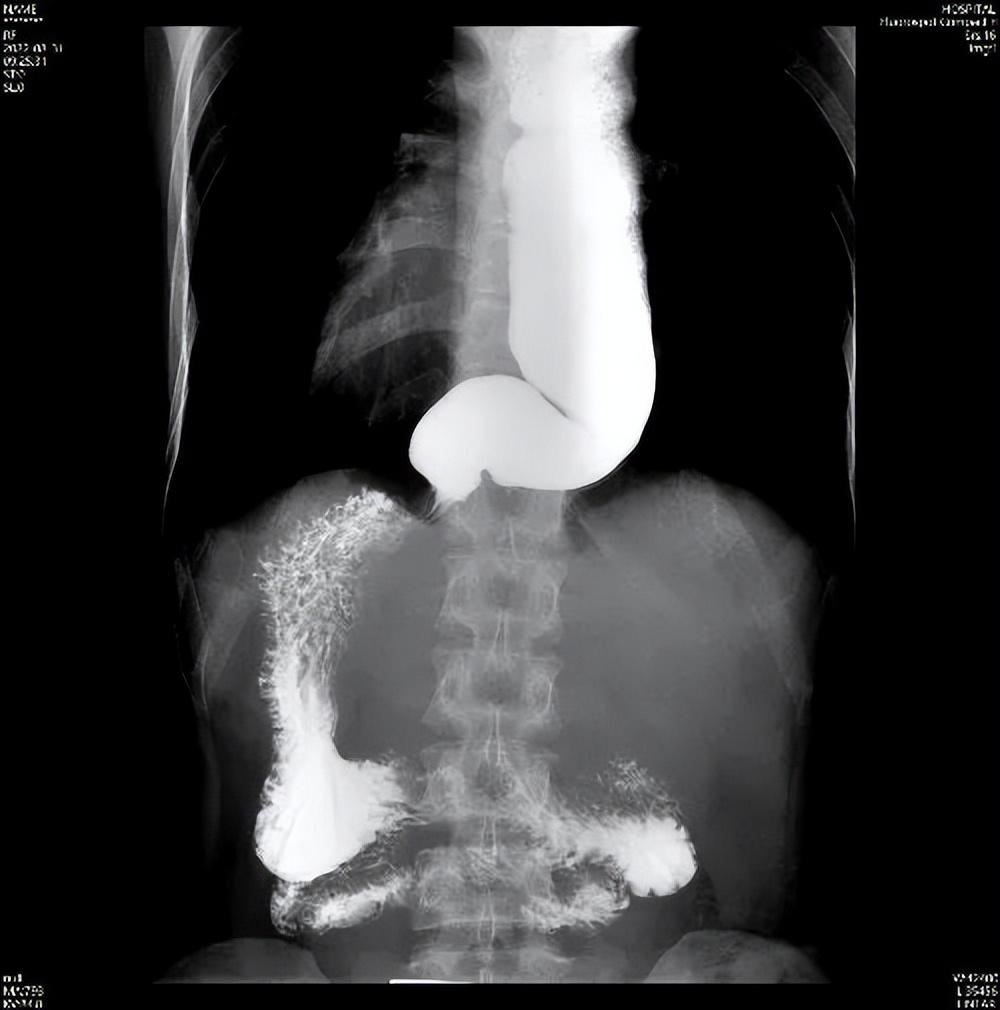

給食管拍“動態 X 光”,你需要喝一種白色的鋇劑(像牛奶一樣的液體),然後在 X 光下觀察它通過食管的過程。賁門失弛緩症患者的賁門部位會出現典型的“鳥嘴樣”狹窄——食管末端像鳥嘴一樣收緊,上面的食管卻明顯擴張,還能看到鋇劑在食管裏“慢慢悠悠下不去”。

鋇餐造影:食管卻明顯擴張扭曲,賁門門部位 “鳥嘴樣”狹窄,鋇劑下去慢慢悠悠。